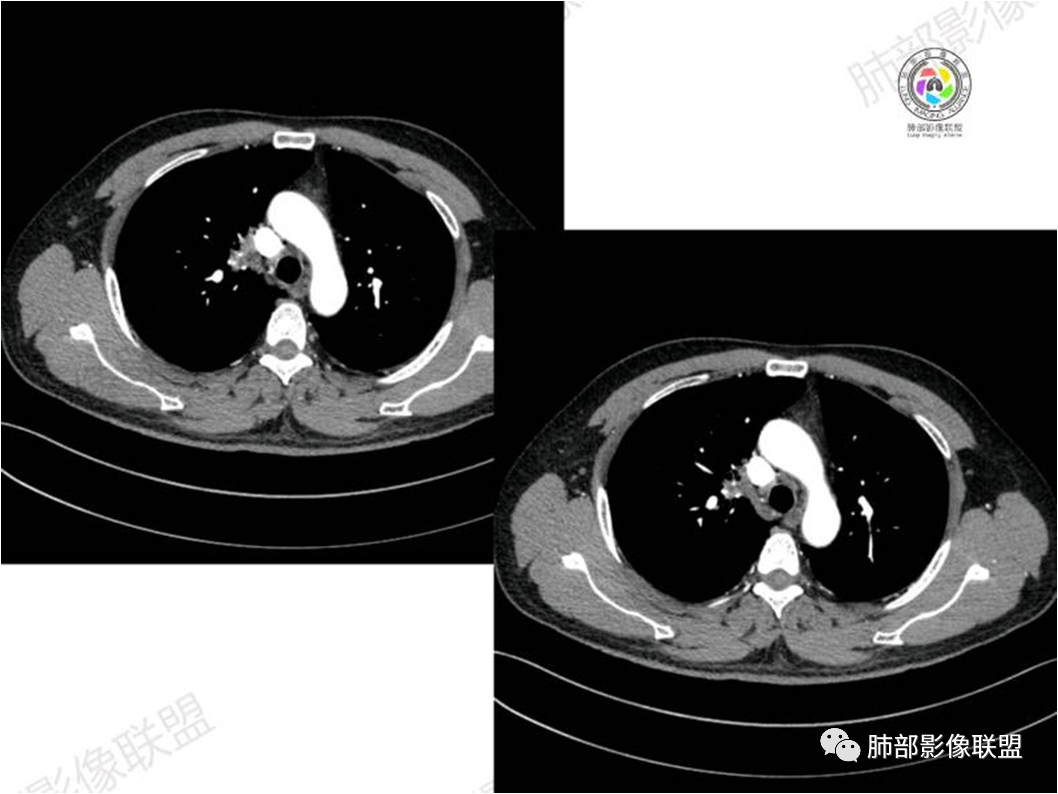

胸部CT:

南边:

病灶紧贴纵隔胸膜

糊墙,胸膜外未见明显侵犯迹象

病灶整体狭长一些

边缘平直、凹陷为主

支气管外侧带的通畅,片内侧带的似乎中近端狭窄,堵塞

内部肺动脉走形还可以

近端支气管壁弥漫增厚

强化均匀

整体炎性的特点比较明显

不踏实的地方:

边上有些毛糙

恶性待排除

恶性:还是淋巴瘤多见一些。